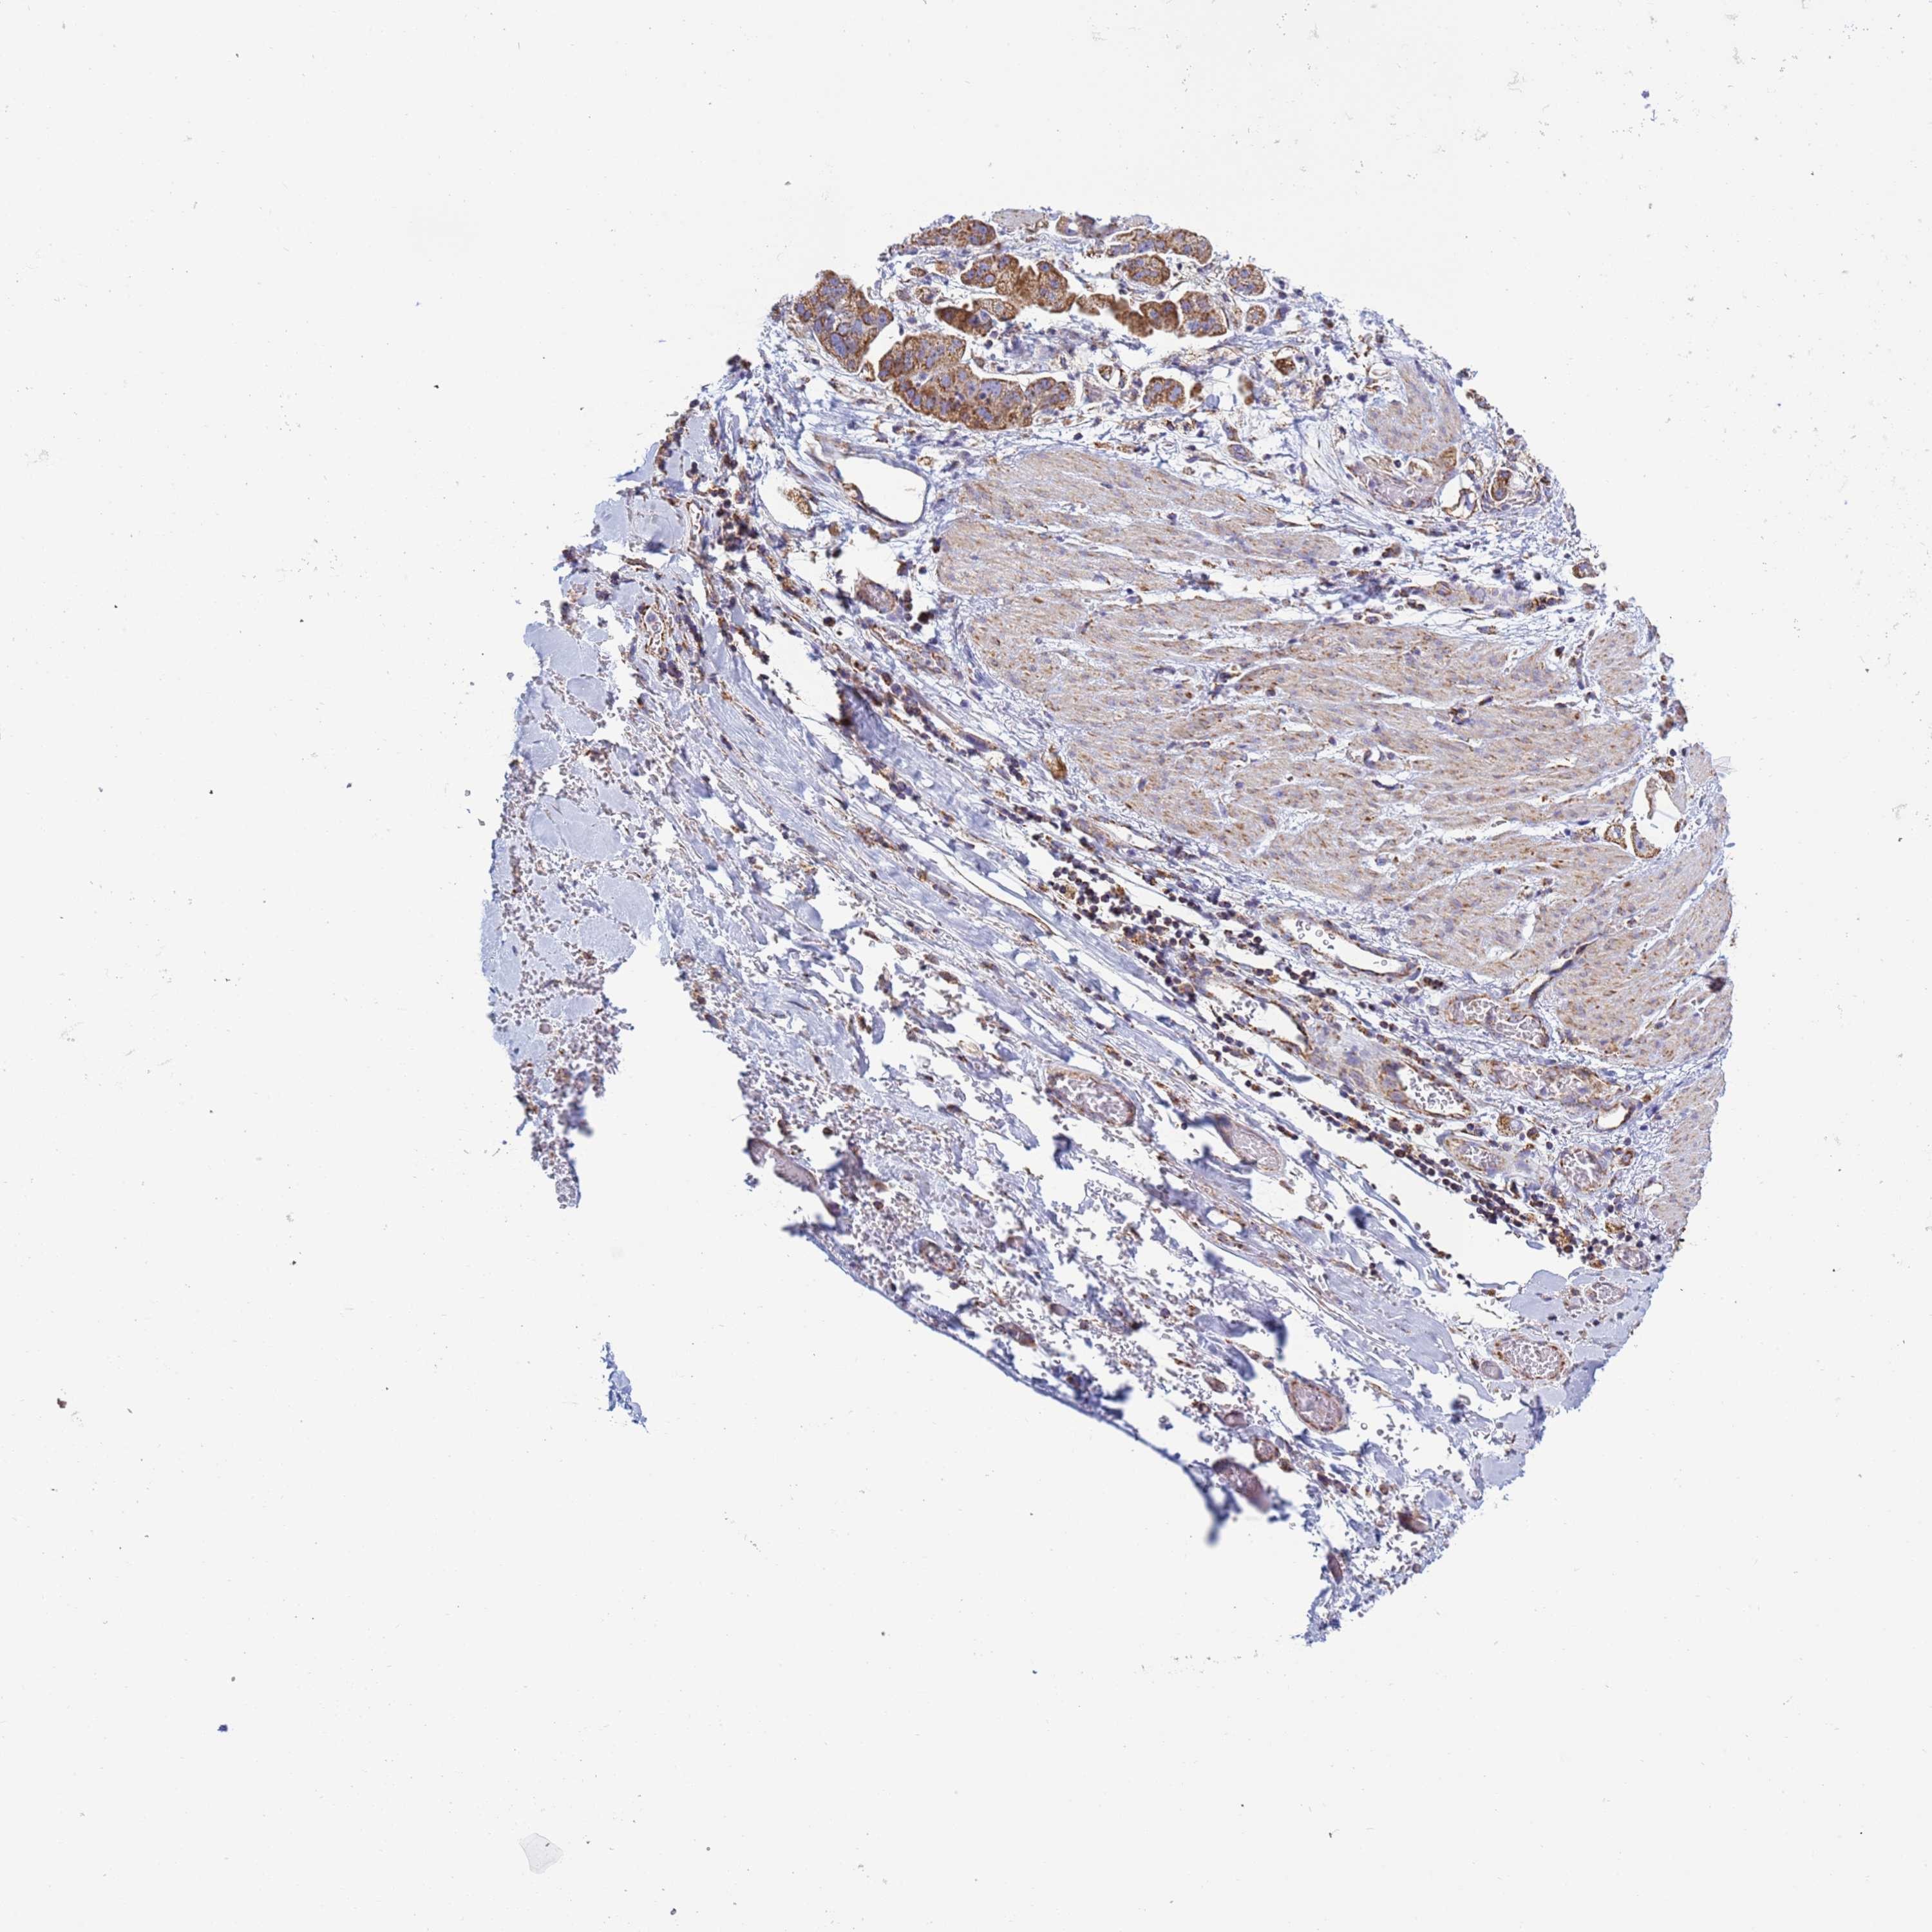

STOMACH CANCER - Protein expressioni

A mouse-over function shows sample information and annotation data. Click on an image to view it in a full screen mode. Samples can be filtered based on level of antibody staining by selecting one or several of the following categories: high, medium, low and not detected. The assay and annotation is described here.

Note that samples used for immunohistochemistry by the Human Protein Atlas do not correspond to samples in the TCGA dataset.

Antibody stainingi

Antibody staining in the annotated cell types in the current human tissue is reported as not detected, low, medium, or high, based on conventional immunohistochemistry profiling in selected tissues. This score is based on the combination of the staining intensity and fraction of stained cells.

Each image is clickable and will lead to virtual microscopy that enables deeper exploration of all samples and also displays staining intensity scores, fraction scores and subcellular localization as well as patient and tissue information for each sample.

Antibody HPA042945

Staining

High

Medium

Low

Not detected

Intensity

Strong

Moderate

Weak

Negative

Quantity

>75%

75%-25%

<25%

None

Location

Nuclear

Cytoplasmic/membranous

Cytoplasmic/membranous,nuclear

Adenocarcinoma, NOS